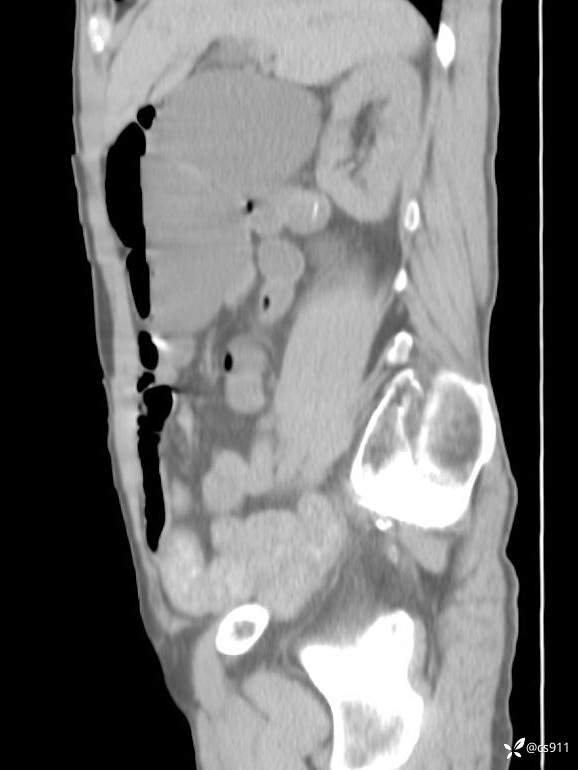

急腹症之急诊CT,原因?答案公布

男,77岁,腹痛、腹胀伴恶心呕吐1天。呕吐胃内容物,非喷射性呕吐,有咖啡色样胃内容物,诉有胃穿孔病史。查体:全腹平,下腹部压痛,全腹无反跳痛,叩诊呈浊音,移动性浊音阴性,肠鸣音减弱,1-2次/分。肛检:直肠未扪及明显肿物,可触及大量粪块。

T 36.6℃ P 80次/分 R 26次/分 BP 100/60mmHg

白细胞(WBC) H 14.55 10e9/L 4-10

红细胞(RBC) 4.58 10e12/L 4.3-5.8

中性粒细胞百分率(NEUT%) H 85.7 % 40-75

血淀粉酶(AMY) HH 1859 U/L 35-135

癌胚抗原(CEA) H 27.44 ng/ml 0-5

呕吐物 潜血试验 * 阳性 阴性

患者轮椅入室检查神志清楚, 能配合摆位和呼吸